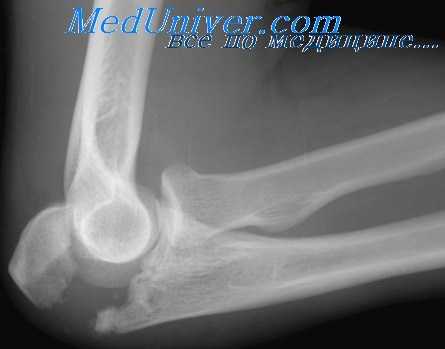

(Слева) На боковой рентгенограмме локтевого сустава визуализируется небольшой отломок перелома кончика локтевого отростка. Края отломка неправильной формы, что отличает это повреждение от несросшегося центра оссификации апофиза.

(Справа) На боковой рентгенограмме у ребенка после падения определяется косой перелом через среднюю точку локтевого отростка с незначительным смещением. Напротив, зона роста локтевого отростка волнистая с выраженным кортикальным слоем по краям. (Слева) На боковой рентгенограмме локтевого сустава после падения на вытянутую руку при согнутом локтевом суставе виден смещенный отломок, оторвавшийся от кончика локтевого отростка. Степень смещения свидетельствует о значительном повреждении трехглавой мышцы.

Боковая проекция локтевого сустава позволяет увидеть перелом локтевого отростка с минимальным смещением без признаков перехода на венечный отросток. Лучеголовчатый и локтевой суставы сохранены. Здесь можно видеть боковую проекцию у этого же пациента. Проведена фиксация стягивающей проволокой. Стягивающую проволоку протянули в виде восьмерки и закрепили двумя спицами Киршнера. При простых переломах локтевого отростка это эффективное лечение, хотя осложнения, связанные с металлоконструкцией, наблюдаются часто. В боковой проекции локтевого сустава определяется сложный перелом дистального конца плечевой кости. Локтевой отросток интактен. Фиксация перелома плечевой кости потребует остеотомии локтевого отростка для доступа к плечевой кости. Здесь можно видеть боковую проекцию у этого же пациента после оперативной репозиции двухмыщелкового перелом плечевой кости. После остеотомии локтевого отростка наложена пластина и выполнена фиксация шурупами.